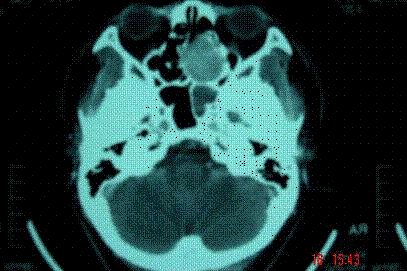

问题 病历摘要: 患者男,37岁,因右鼻塞伴涕中带血4个月入院,患者4个月前始右鼻塞,为间断性,偶有涕中带血,时有流脓性分泌物,并症状渐渐加重。但发病以来患者无头痛、面部麻木和疼痛,无复视及流泪,张口正常。检查:右侧鼻腔总鼻道可见表面光滑、质中、粉红色肿物,触之不易出血。鼻咽黏膜光滑,未见新生物和黏膜糜烂。颈部未及淋巴结肿大。 为了确诊,需做哪些辅助检查?

选项 A、鼻腔鼻窦内窥镜检查 B、生化检查 C、胸正位片 D、鼻窦CT E、鼻窦MR F、鼻咽MR G、胸部CT H、鼻咽CT

答案 ADE